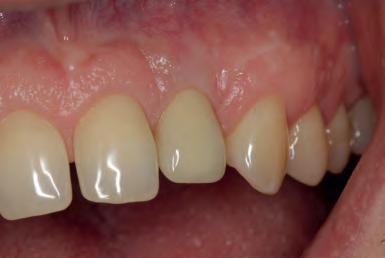

MANAGEMENT OF PERI-IMPLANTITIS IN THE AESTHETIC ZONE

The management of peri-implantitis cases in aesthetically demanding areas is a highly relevant clinical challenge due to the increased risk of mucosal recessions subsequent to the treatment. The exposure of the implant surface may result in an aesthetically unacceptable outcome. Thus, the additional goal of peri-implantitis management in aesthetic areas is the preservation of the esthetics.

The lecture will elaborate on the remodeling process that peri-implant tissue undergoes following the surgical peri-implantitis treatment. It will further address the step-by-step surgical treatment protocol for the management of peri-implantitis cases in the aesthetic zone and the rationale for soft-tissue grafting as part of the treatment protocol. Clinical scenarios resulting in unacceptable aesthetic outcomes requiring implant removal and the “second-round” implant planning will be further discussed.